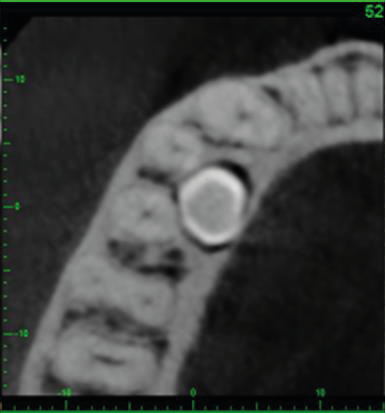

The crown of the supernumerary tooth is lingual to the middle thirds of the roots of LR4 (44) and LR5 (45), below a thinned lingual cortical plate (image 3). The pericoronal follicle space is of normal size.

3. Axial cross-section showing the crown of the supernumerary tooth (image viewed from below).